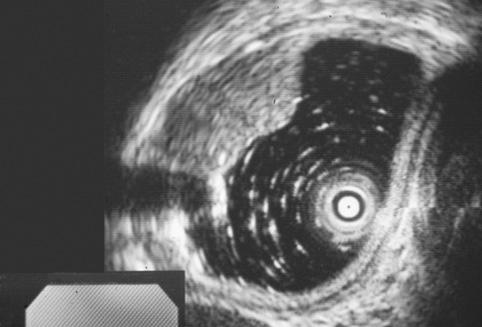

Criteria of Hist.ClassificationMalignant epithelial tumor/Squamous cell carcinoma

LocationEsophagus/Middle third

Technique, MethodUltrasonography

Macroscopic TypesType 0/IIa (IIa+IIc) Superficial elevated and depressed type

Size15 - 19

Depth of Tumor Invasionsubmucosa